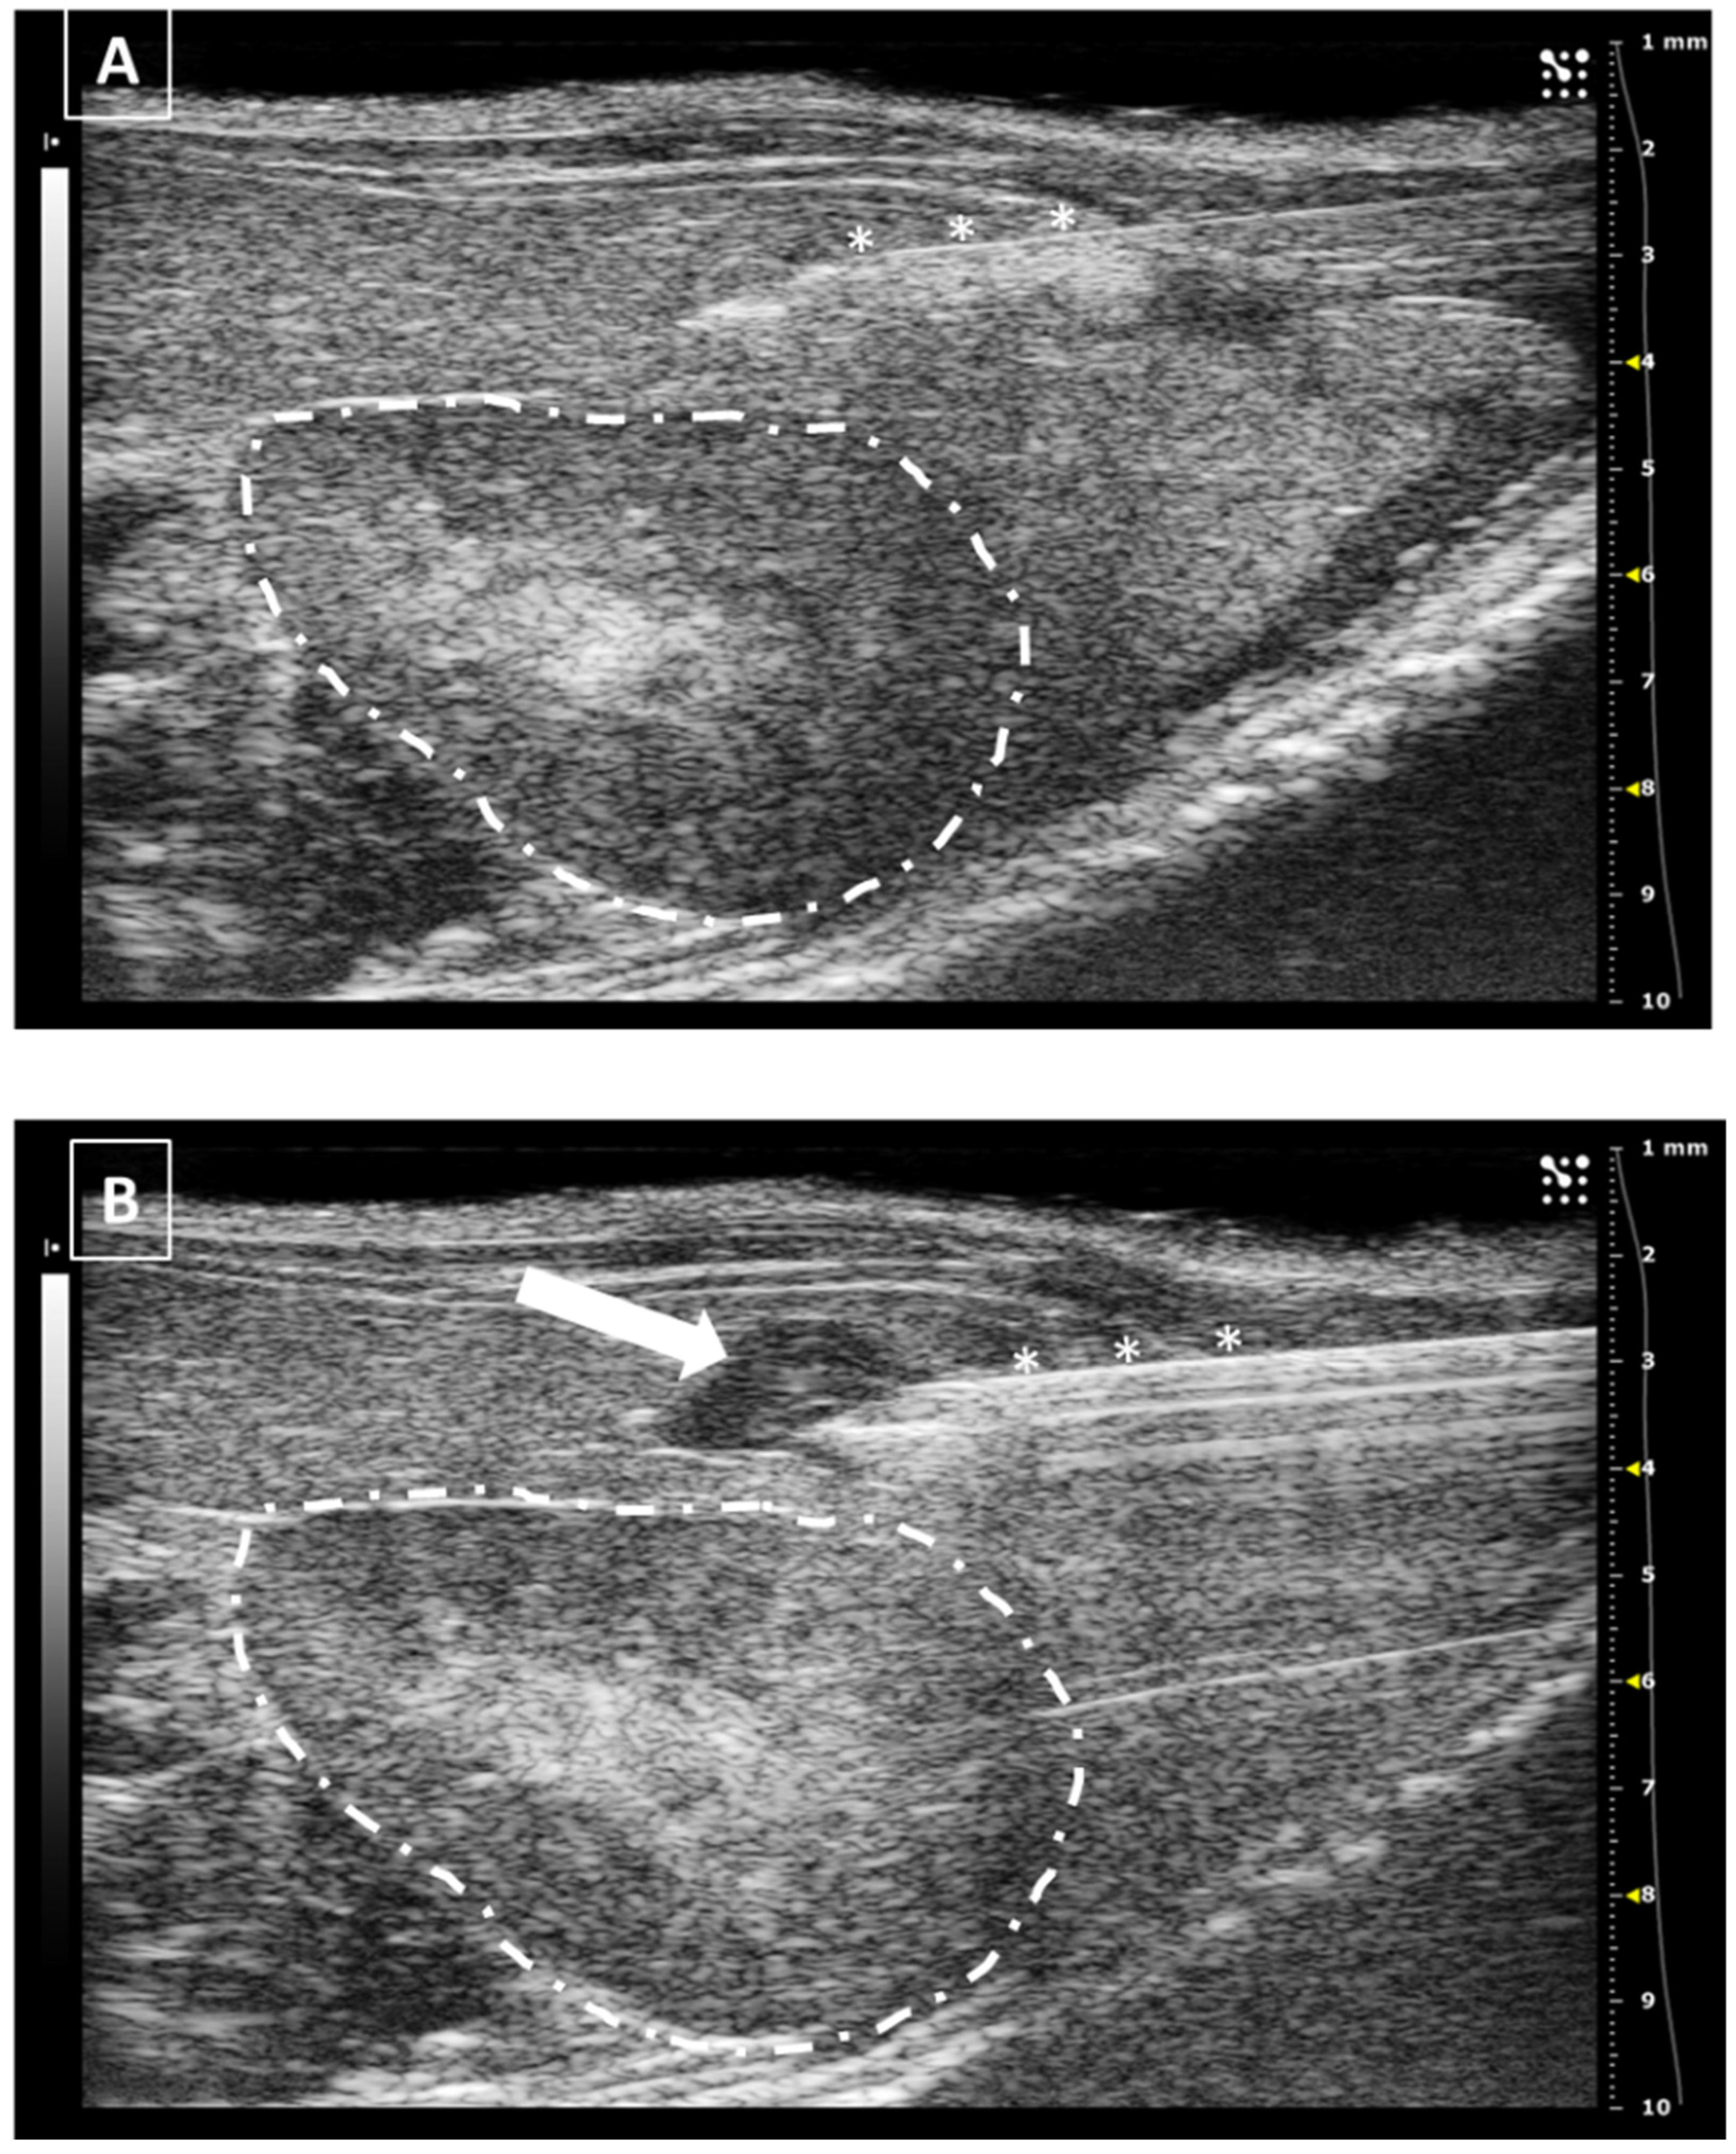

The needle can be seen inside the left ventricle as a hyperechoic linear structure with reverberation artifacts in an anechoic background. During the injection, we will be able to see some small hyperechoic dots coming from the needle. These are microbubbles created during the needle filling. These dots will confirm the correct injection in the anechoic ventricular cavity. Once the injection is completed, the needle can be removed. An example of an intracardiac injection can be seen in Figure 3.

The duration of this process depends on the expertise of the user. An experienced ultrasonographer can do the injection in less than a minute. The major risk of this procedure is the incorrect injection in the right ventricle, the lung, or the mediastinum. We will not see the hyperechoic bubbles arising inside the left ventricle. Other less frequent errors can be damaging the aorta the cava vein or any of the cardiac atriums. In these cases, we will see an acute intrathoracic hemorrhage.

Figure 3. Intracardiac injection. (A) Preinjection image. Needle is marked with white asterisks and left ventricle area is surrounded by a dashed line. Lung artifact is labeled with white arrows. (B) Injection moment. Multiple white dots (marked with white arrows) inside the left ventricle correspond to microbubbles injected with the suspension. Images obtained with 40 MHz frequency.